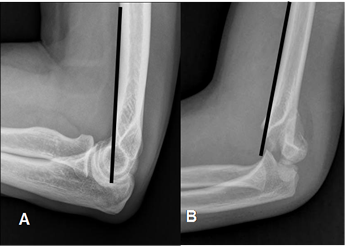

Fig 29. Signo de la línea humeral anterior en Rx lateral.

A: Línea normal, que cruza el capitel.

B: Fractura supracondilea con desplazamiento del capitel, que no es cruzado por la línea humeral anterior.